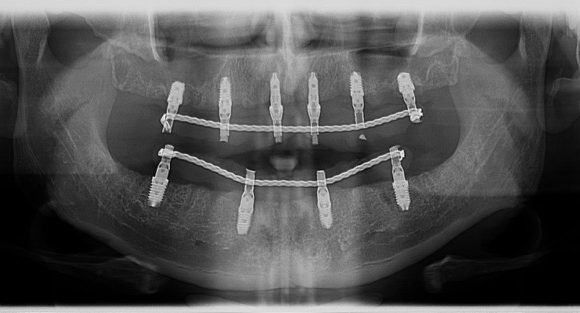

Današnji Dental Studio Flegar eden vodilnih centrov za vsadke na Hrvaškem in tem delu Evrope, in drugi. Flegar na področju implantologije zobozdravstva in oralne kirurgije, tesno sodeluje z Biotechnology Institute (ZTI), ki je “opinion leader” in je trenutno v tujini zaključil podiplomski študij na področju dentalne implantologije.

Visoko usposobljeno osebje in sodobne tehnologije so osnovni temelj uspešnega dela. V naši ordinaciji, implantante v postopkih, ki jih uporabljamo najboljše vrhunskie PRGF-Endoret® biotehnologije in sodobne diagnostične metode in najbolj naprednih instrumentov in opreme.

- uspeh postavitve implantata več kot 99,4%